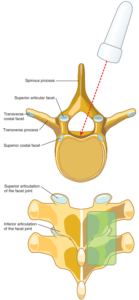

در روش میدلاین، سوزن از خط وسط ستون فقرات به سمت فضای اپیدورال هدایت میشود.

این روش، روش ارجح بلاک اپیدورال سینهای است، اما بسته به شرایط بیمار، روشهای جایگزین نیز ممکن است انتخاب شوند.

سر بیمار روی تکیهگاه قرار داده میشود تا فاصله بین زوائد خاری مهرهها افزایش یابد.